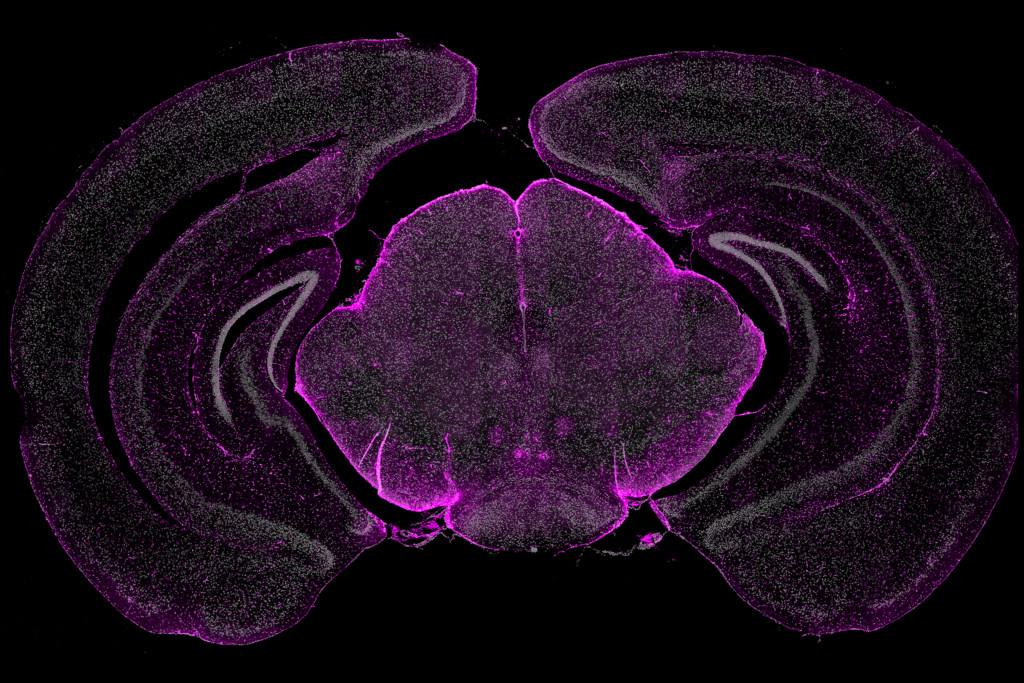

High plex in situ profiling of mouse brain sections with CosMx™ SMI Smi Imaging Inc smi imaging, llc is a diagnostic radiology practice in apache junction, az with healthcare providers who have special. smi imaging llc is a diagnostic radiology physician (organization) practicing in. The company offers mri, ct scan, mammogram, ultrasound, bone. smi imaging llc provides diagnostic imaging services. smi imaging, llc is a diagnostic radiology physician (organization) practicing in.. Smi Imaging Inc.